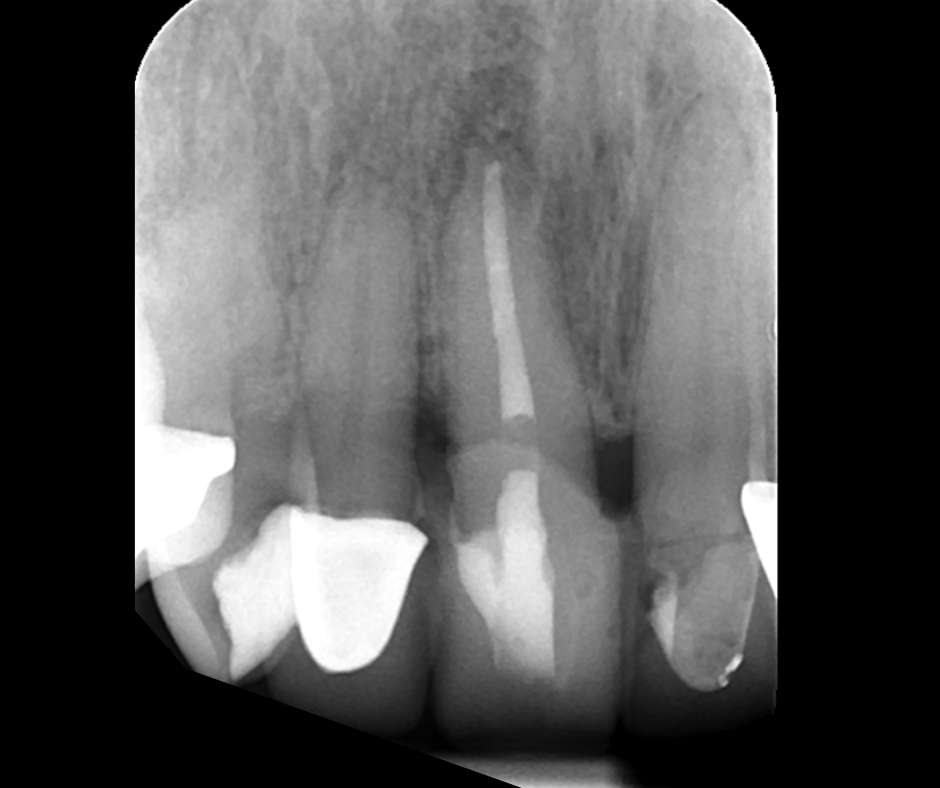

This course focuses on modern single-file endodontic systems, guiding participants through diagnosis, case assessment, access cavity design, canal location, root canal system preparation, and obturation techniques.

• To understand the importance of achieving patency and mechanical glidepath with hand & NiTi instruments

• To gain confidence in mechanical preparation using rotary and reciprocating NiTi shaping instruments

11.45 – 13.00 – Contemporary NiTi 1: Canal Location, Scouting, Patency and Glidepath

14.00 – 16.00 – Contemporary NiTi 2: Mechanical Preparation and Update on Irrigation